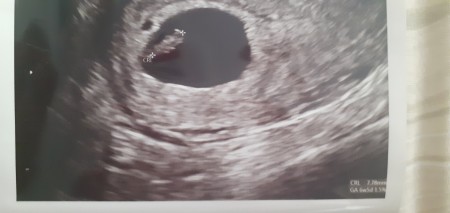

Bebeğin Kalp atışı Kaçıncı Haftada Başlar

Bebeğin Kalp atışı Kaçıncı Haftada Başlar.

fetal bebek kalp atisi ne zaman duyulabilir riskler ve onlemler nedir